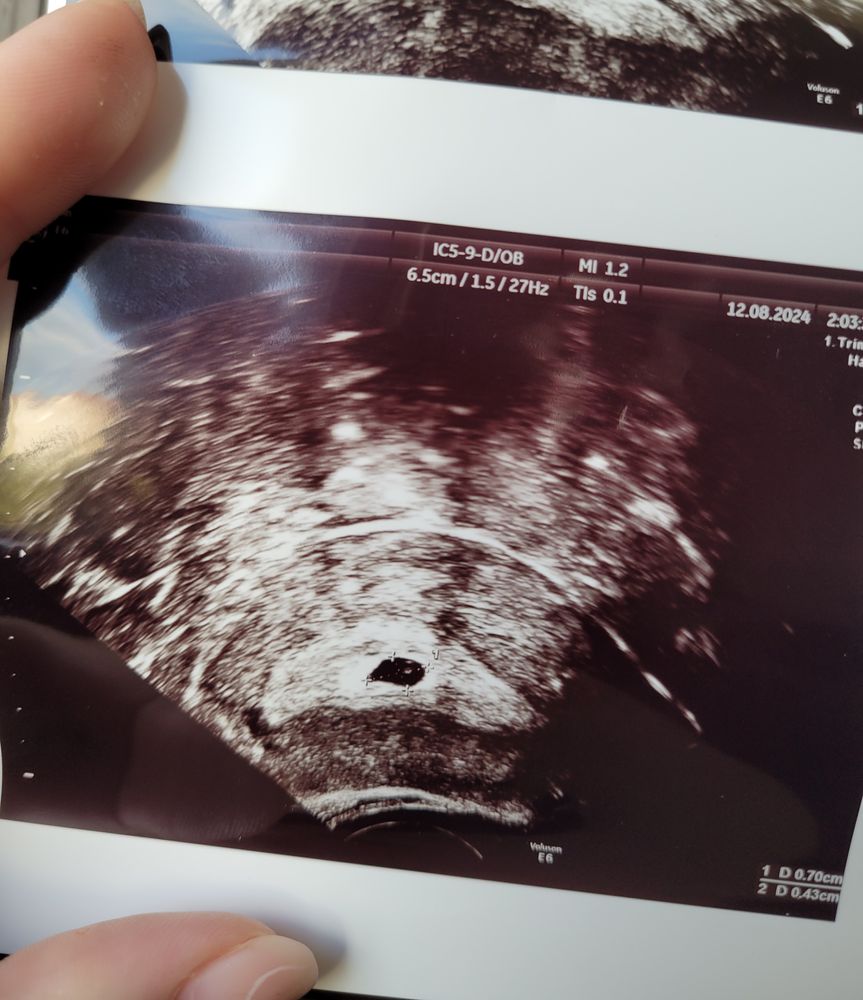

Ретрохориальная гематома на 18 дпп

На 22дпп полилось, была к этому готова, мужа за транексамом отправила, вызвала скорую, накануне нагулялась пешком, видимо перенапряглась. С транексама начало рвать, заменили на уколы этамзилат. В итоге месяц работала из дома, из кровати выползала только в туалет, помыться и поесть. Через 2-3 недели гематома рассосалась, была 50% от эмбриона. Все хорошо, от ЭКО частая побочка слабые сосуды, лопаются, иногда даже не рядом с эмбрионом. Будьте к это у готовы просто, это вариант нормы. Берегите себя, меньше физ нагрузки, больше отдыхать, лежать.

Гематома была но без выделений, назначали прогестерон (дюфастон или утрожестан) до 16 недель.